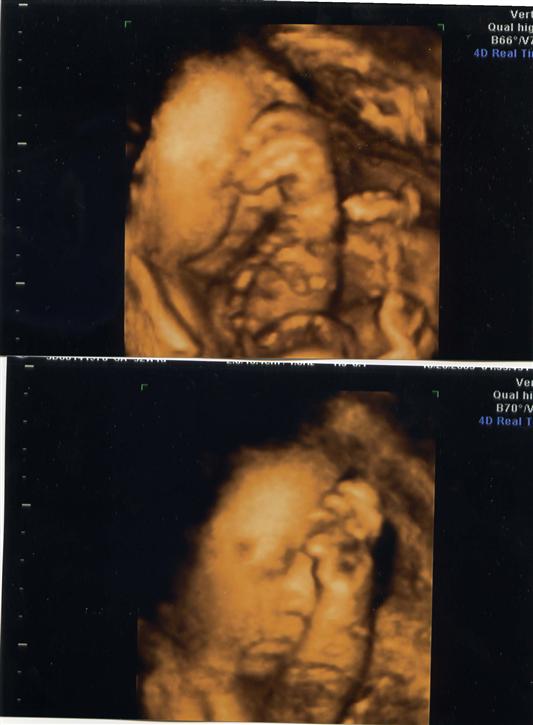

Got my 4-D Sonogram Done (w/PICS)!!!

So here's my little munchkin, we don't want to know the sex, but I think it looks like a boy.

I had the sono done in NYC w/ Dr. Kevin Jovanovic He was SO nice & made the experience a lot of fun for DH & I.

Here ya go! Image Attachment(s):

Those are so amazing. I can't believe how clear and up close they are. Wow, that must have been so much fun. My vote would be a boy

Aww, how precious. I love the 3rd pic where he/she is smiling

You must have said something funny...look at him/her smiling!

he/she is playing peek-a-boo with you!

That is amazing. In one pic the baby looks like he/she is smiling.